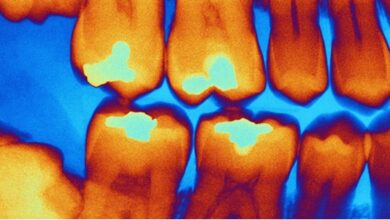

La tomografía computarizada de baja dosis (LDCT) es actualmente la herramienta más eficaz para detectar el cáncer de pulmón en sus primeras etapas. A diferencia de la radiografía tradicional, la LDCT puede identificar lesiones muy pequeñas antes de que aparezcan los síntomas, lo que permite iniciar tratamientos oportunos y menos invasivos.